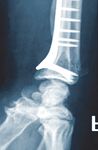

C1 Fraktur, Versorgung mit volarer Platte (breit) und Ulna-Hakenplatte

Präoperativ

Postoperativ

Klinischer Fall und CT-Aufnahmen mit freundlicher Unterstützung der

Klinik und Poliklinik für Unfall-, Hand- und Wiederherstellungschirurgie

Universitätsklinikum Gießen und Marburg GmbH